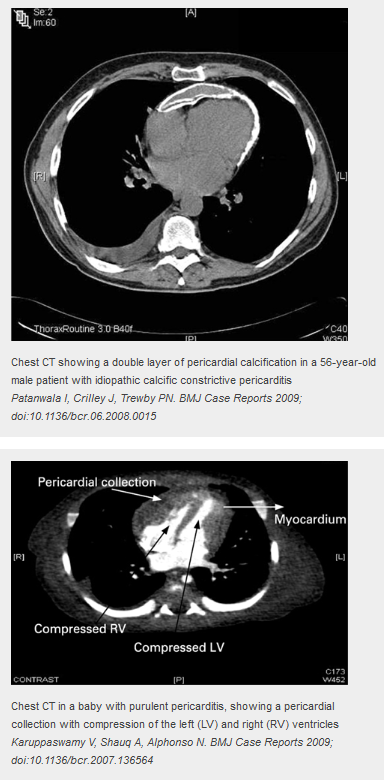

There are 2 layers of pericardium (visceral and parietal). These 2 layers are normally distensible with a small space between them containing fluid. However, in constrictive pericarditis they become inflamed and they fuse.

Late disease i.e. calcification, AF, cachexia - SURGICAL - refer to cardiothoracics for pericardiectomy [or medical e.g. diuretics if not suitable candidates for surgery]